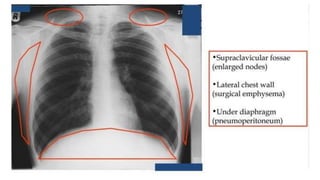

Hidden areas…